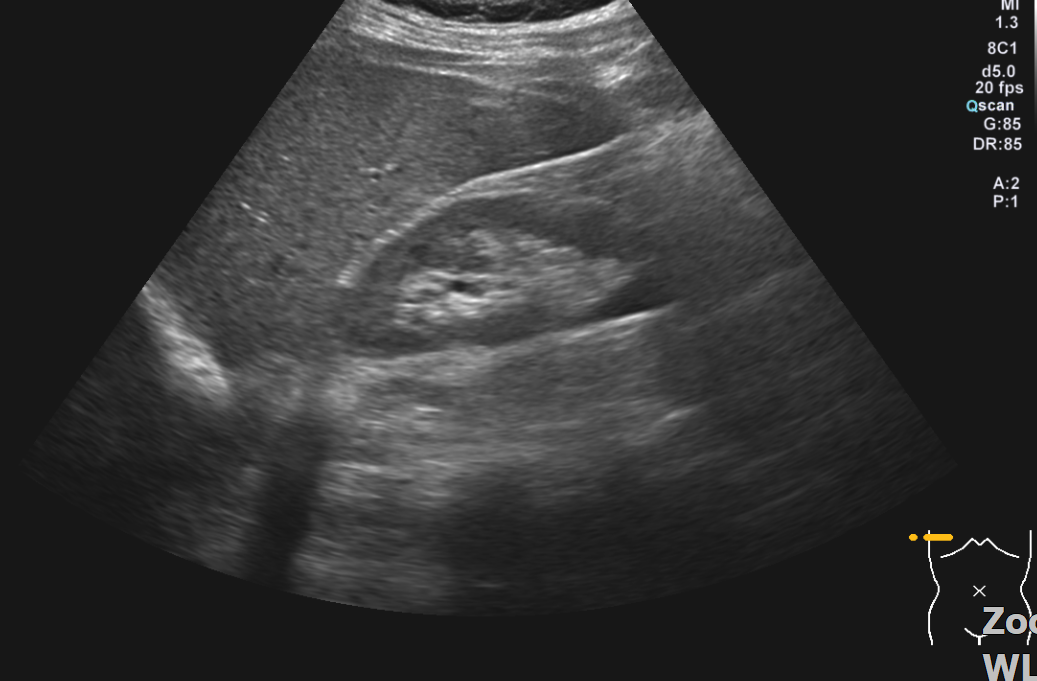

복부초음파 검사했는데요 초음파상 오른쪽신장 부근 사진인데 신장물혹이 보이나요?

혹시 복부초음파 오른쪽 신장부근 사진몇장올리는데.. 혹시 물혹이 보이시나요?

• 2번 째 사진

복부초음파 사진 여러 장 올린 것에 신장낭종은 잘 보이지 않는 것 같습니다